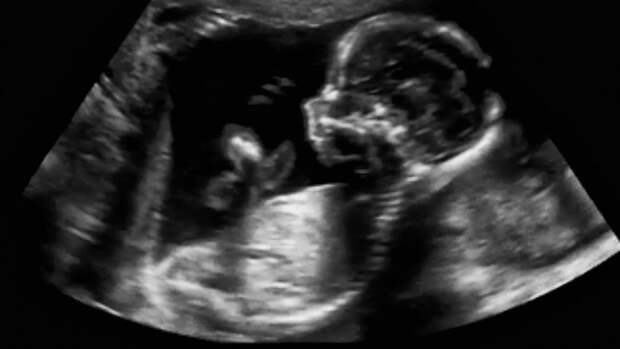

Клиент службы и его бывшая супруга, столкнулись с проблемой бесплодия во время брака. Они обратились в клинику с целью проведения процедуры экстракорпорального оплодотворения (ЭКО).

После сдачи биоматериалов и проведения процедуры экстракорпорального оплодотворения у женщины не наступила беременность.Было создано избыточное количество эмбрионов, чем требовалось для процедуры. Бывшие супруги подписали Информационное добровольное согласие на проведение процедуры криоконсервации и хранения эмбрионов человека в частной клинике. Таким образом, одной из услуг клиники было хранение криоконсервированного биоматериала (эмбрионов). Для создания эмбрионов использовался биоматериал обоих супругов.